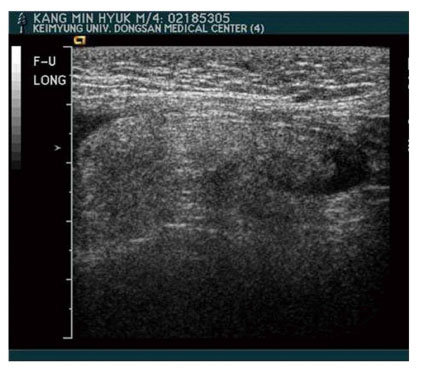

Fig. 1). On operation, we found a bulbous hemorrhagic fat mass attached to the anterolateral portion of the spermatic cord structures and a transparent thin hernia sac located in anteromedial portion of the cord without containing structures (

Fig. 2A). The hemorrhagic fat lobule extended to the level of the constricted internal ring and was obviously normal in color above the internal ring (

Fig. 2Intraoperative findings showing a bulbous hemorrhagic fat mass on the anterolateral portion of the spermatic cord structure and a transparent thin hernia sac in anteromedial position of the cord without containing structure (A). The fat lobule showed obviously normal in color at the level of internal ring (B).